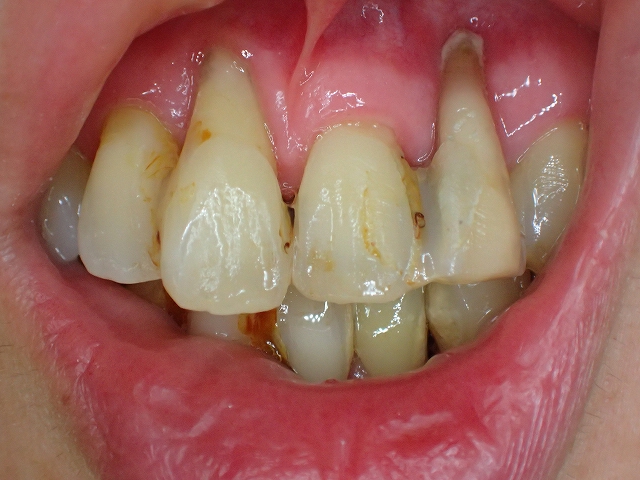

歯の周囲の歯周組織は破壊され

相対的に歯が長くなっています。

歯周病固定 実例3 長期にわたって観察管理・予防処置

定期整備を続けてゆくと、なんと症状は緩解して再生してくる

2026年2月

固定と、定期整備を続け、歯周病はむしろ緩解

しています